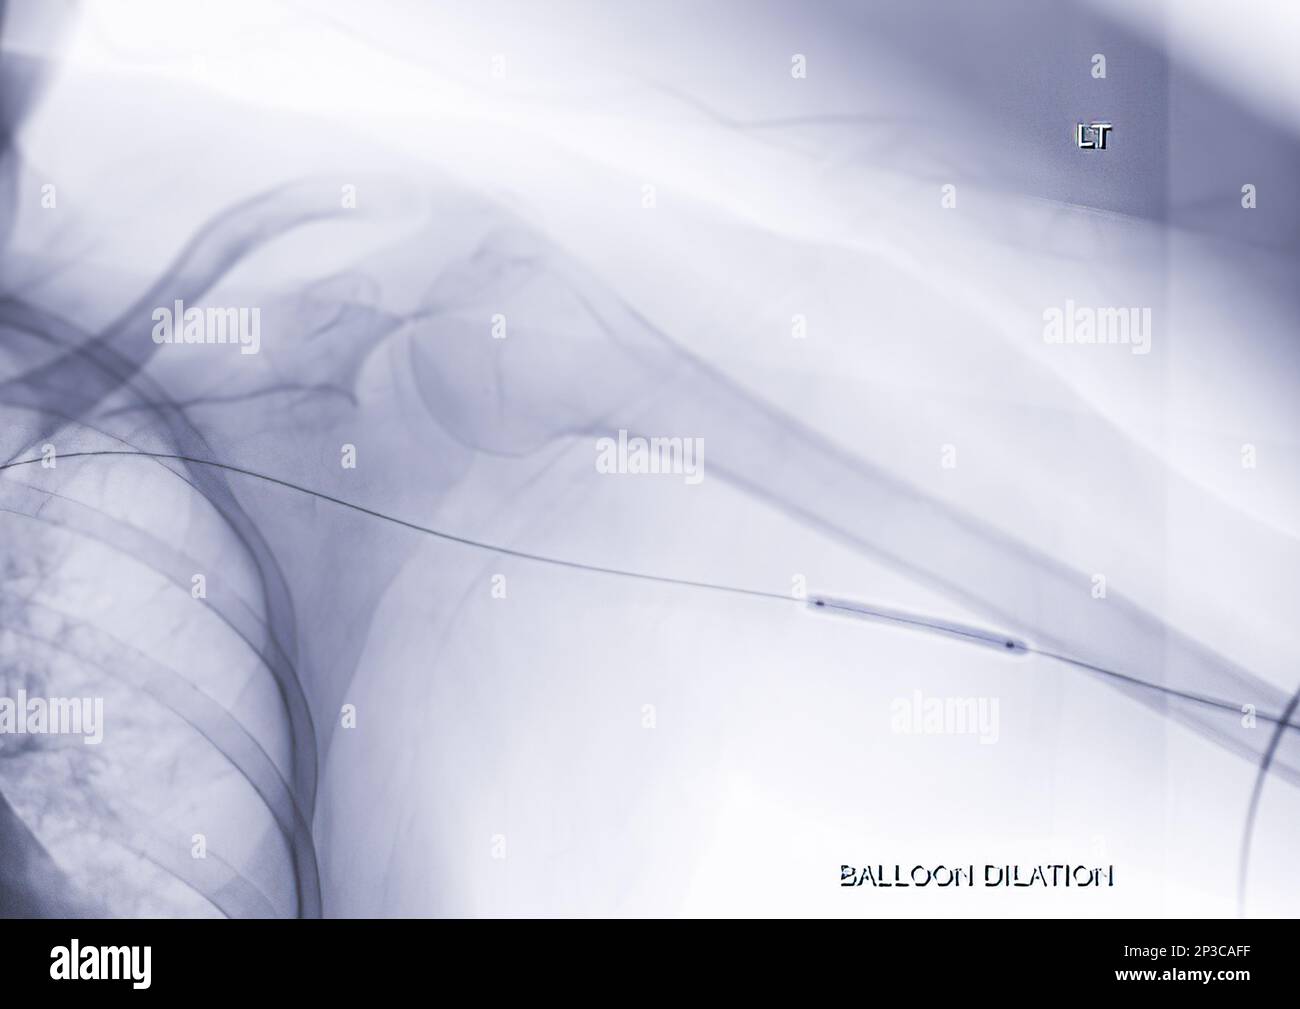

Angiographic images demonstrate the atherectomy, balloon angioplasty